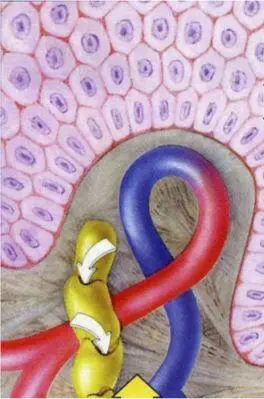

Структурные основы лимфообразования (схема): подвижные межэндотелиальные контакты лимфатических капилляров устроены и функционируют как внутристеночные клапаны с подвижной внутренней и фиксированной (якорными филаметами) наружной «створками»